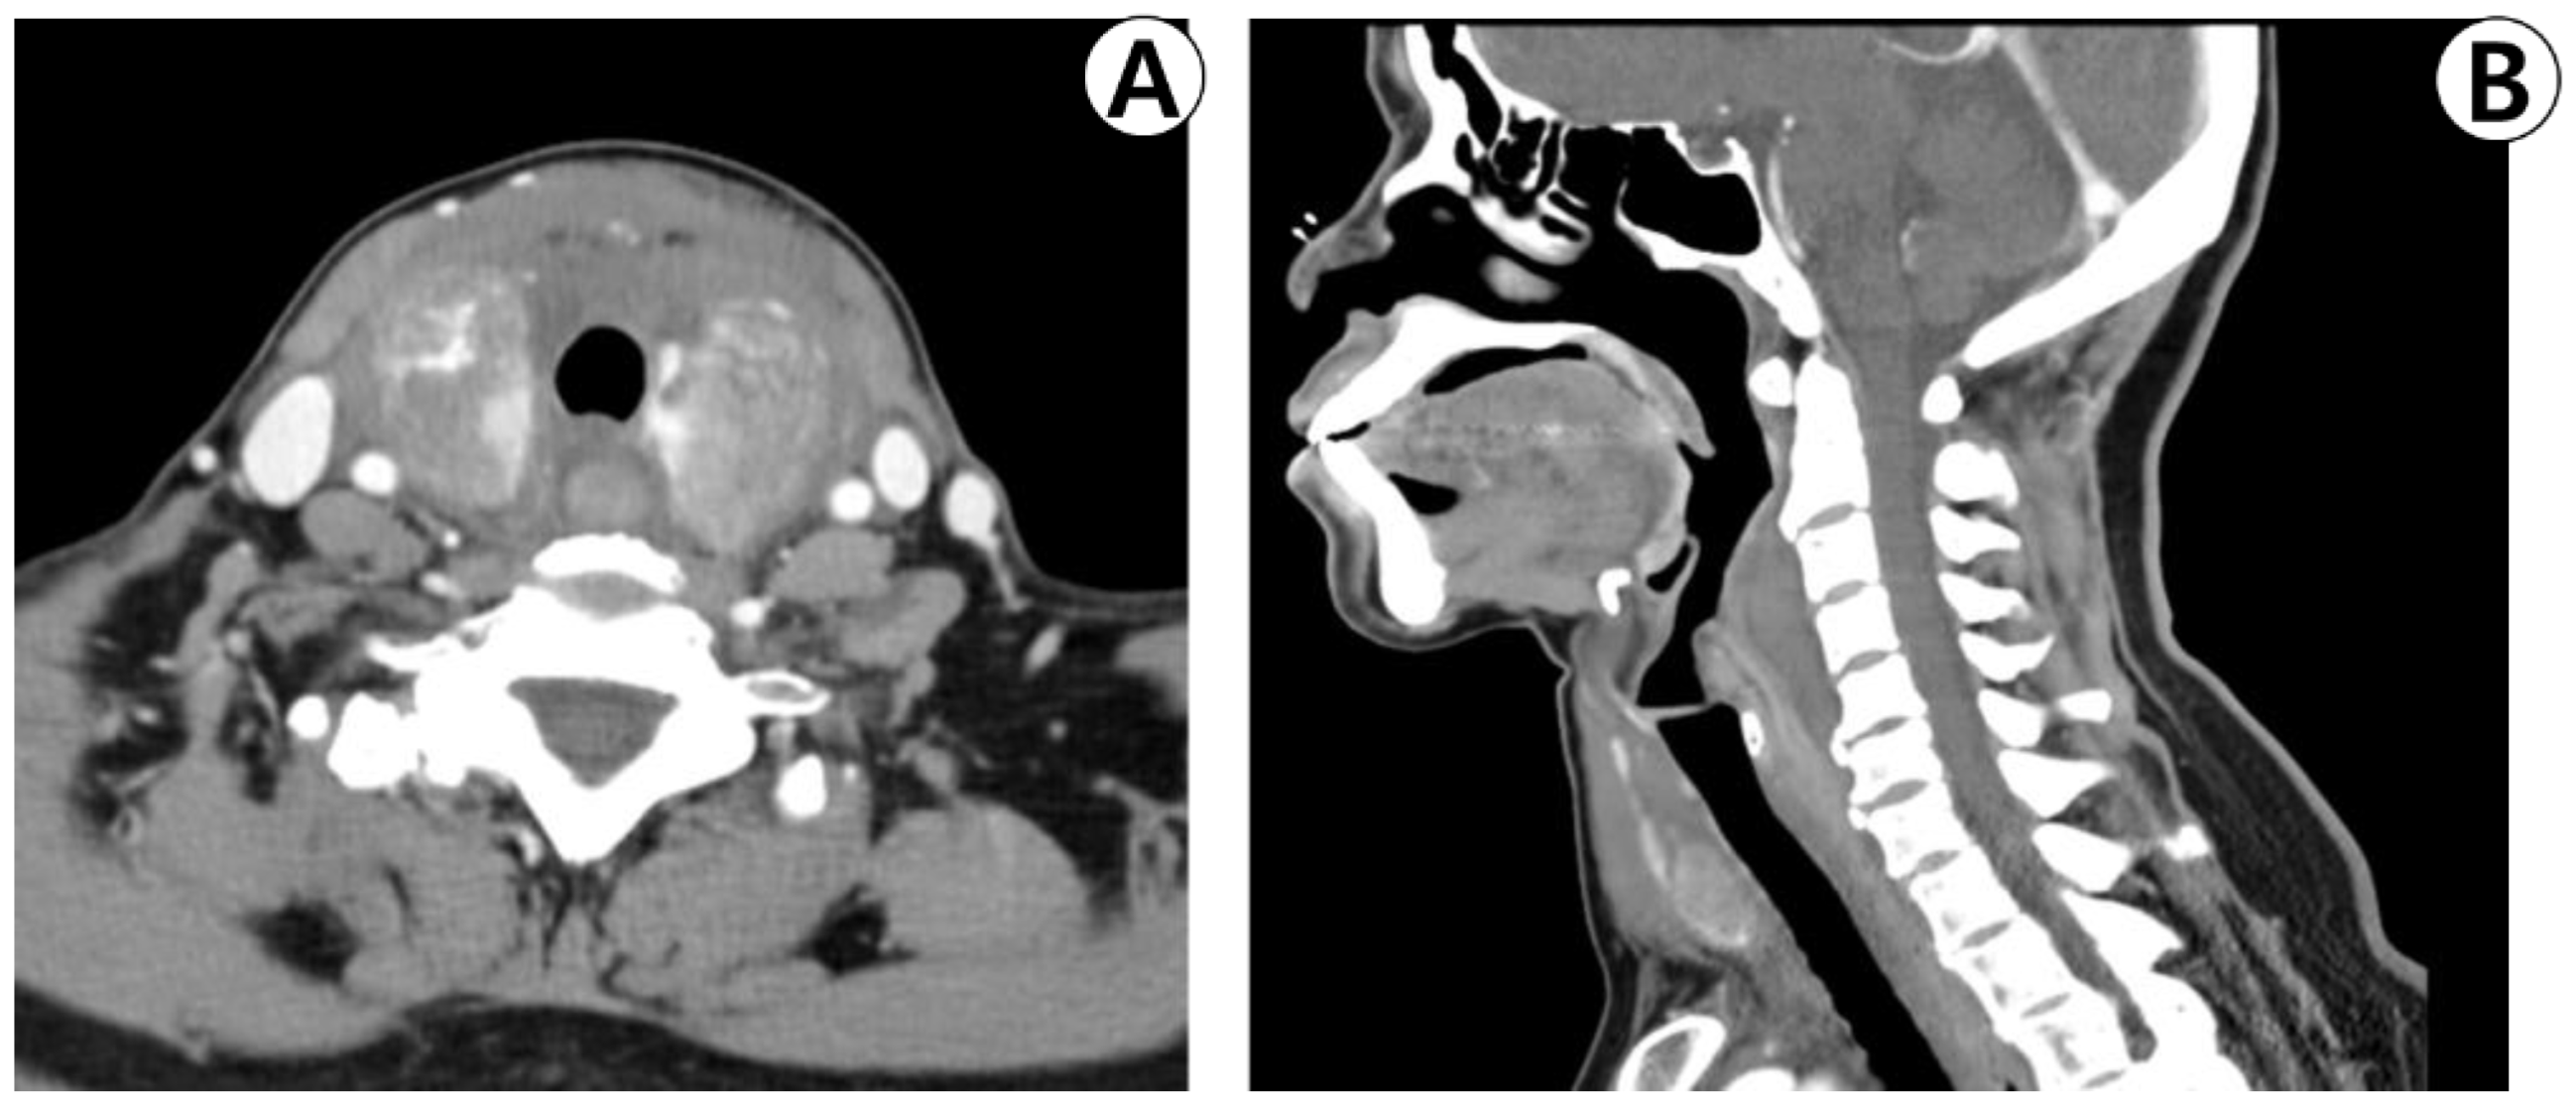

Both thyroid lobes exhibited diffuse swelling and heterogeneous contrast enhancement on neck computed tomography. No airway obstruction was observed. The anterior neck, parapharyngeal space, retropharyngeal space, and upper mediastinum exhibited increased soft-tissue density without any contrast enhancement (Figure 3A,B).

Figure 3. Enhanced neck computed tomography. (A) The axial view shows diffuse swelling and heterogenous enhancement of both thyroid lobes. (B) The sagittal view shows diffuse non-enhancing soft-tissue density lesions of the retropharyngeal space and superior mediastinum.